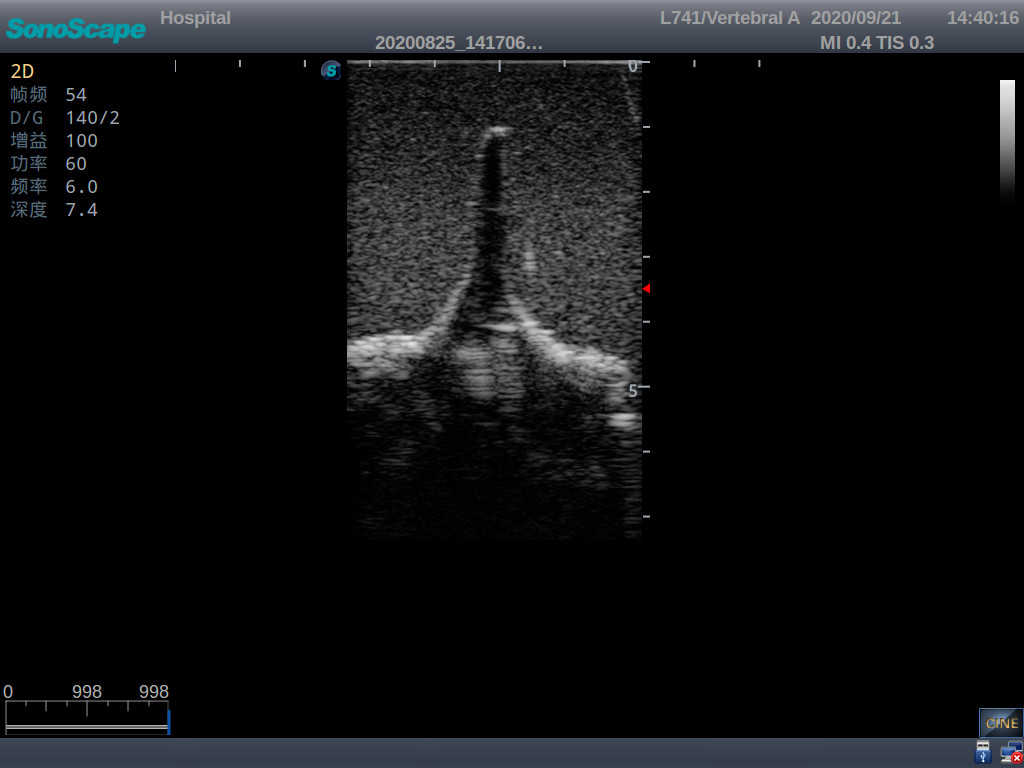

This model is an ideal choice for ultrasound-guided adult lumbar puncture training with true-to-life skin feel and touch, accurate anatomical structures as well as real clinical ultrasound images. Realistic resistance to needle tips and correct landmarks provide excellent hands-on experience.

Accurate anatomical structure of L1-L5 and the vertebral canal

2)  Real clinical ultrasound images

3)  Compatible with various real ultrasound machines

1)   Ultrasound-guided lumbar puncture practice